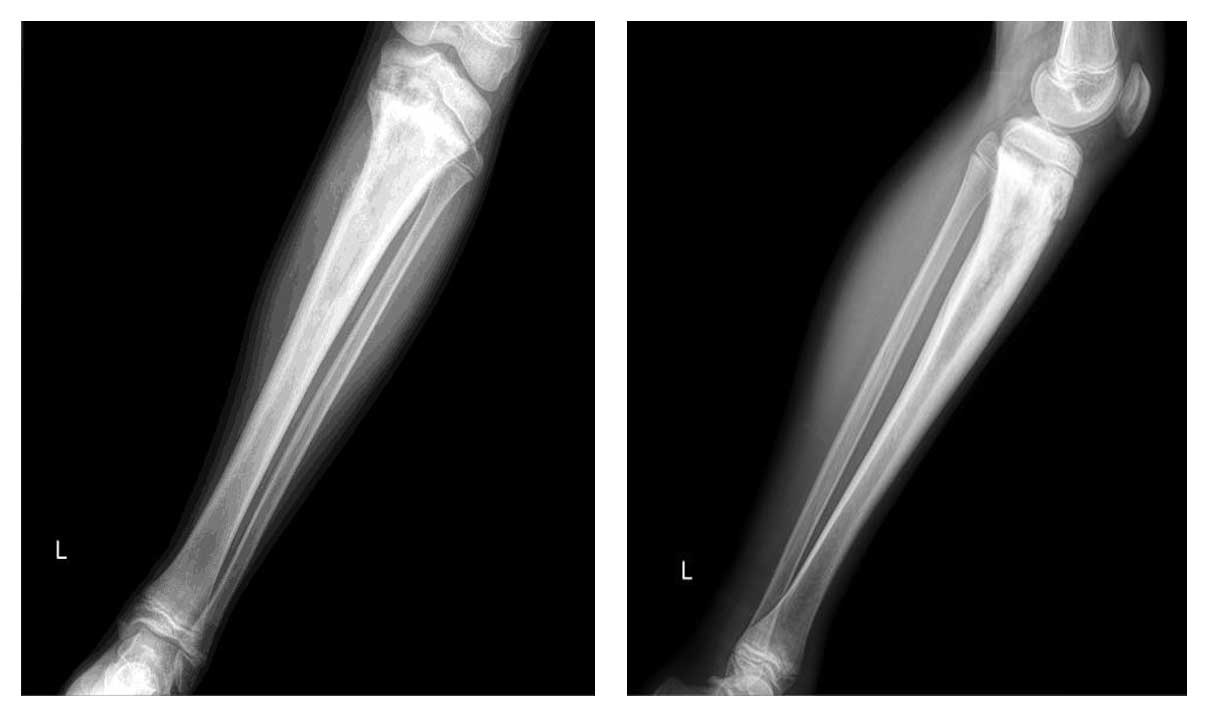

Ameliyat Öncesi: Röntgende proksimal tibiada düzensiz sınırlı sklerotik lezyon görülmekte.